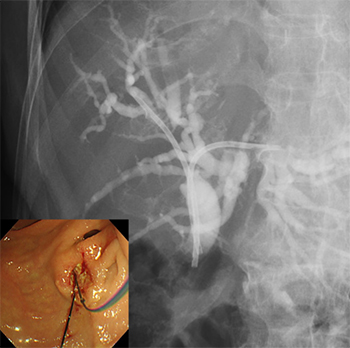

内視鏡的逆行性胆管膵管造影(ERCP)・超音波内視鏡(EUS)による高度な診断治療

悪性肝門部胆管狭窄に対する

内視鏡的インサイドステント留置術

内視鏡的メタルステント留置術